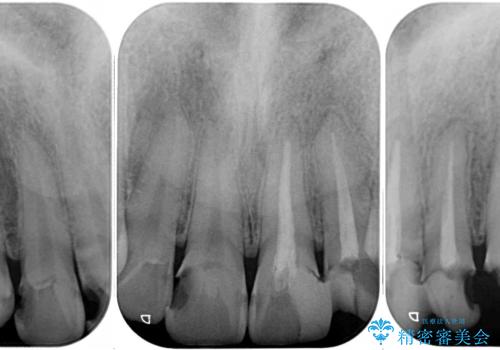

むし歯は歯肉内にまで進行していると外科処置が必要となりますが、ギリギリの位置でとどまっていたため、速やかにオールセラミッククラウンにて補綴治療することとしました。

むし歯は多かったものの、歯肉の腫脹はそれほどなかったため、最小限の治療回数で治療を終えることができました。